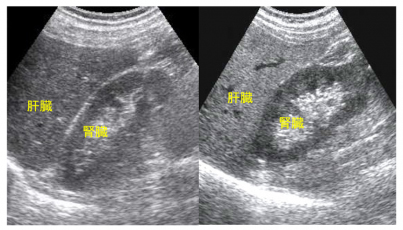

⑤正常肝と脂肪肝の超音波画像

(左)正常肝、(右)脂肪肝

脂肪肝の肝臓は正常肝に比べ白色調です